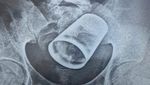

Pria 73 tahun mengeluh benjolan perut, dan operasi menemukan benda semacam botol silindris panjang di dalam kolon desenden. Benda asing dikeluarkan lewat pembedahan kolotomi. (Foto: Malaysia Family Physician)